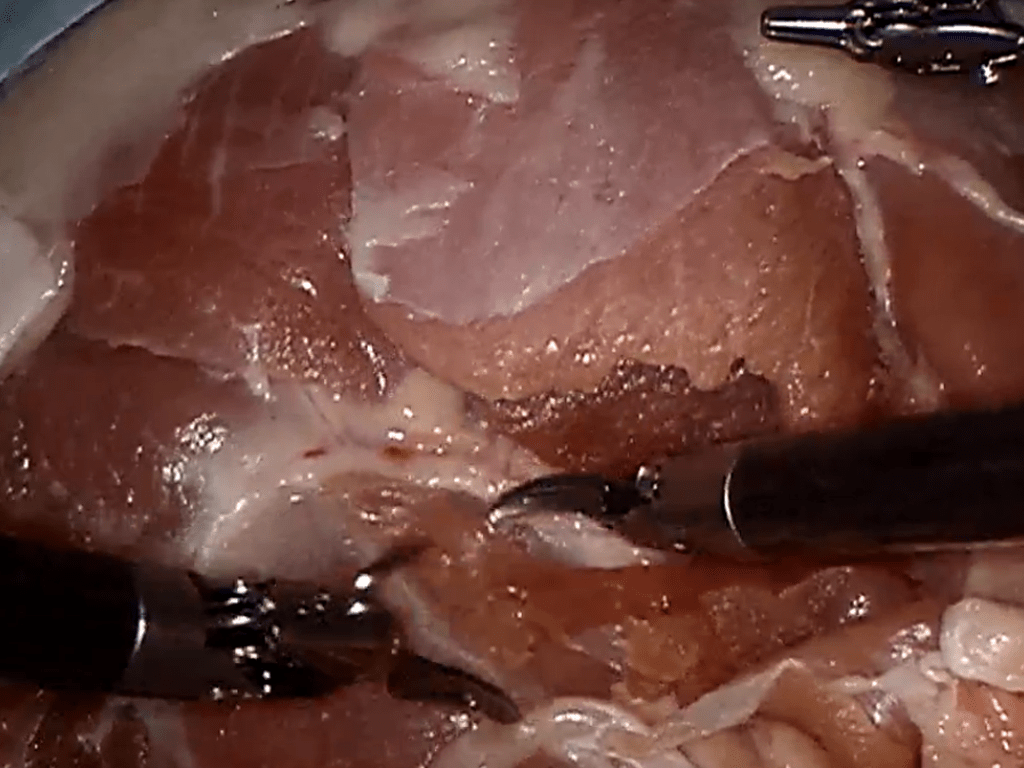

Reduction in Surgical Site Infections (SSI)

Reduction in Surgical Site Infections (SSI) Clinical Initiatives to reduce Surgical Site Infections - Children's Hospital desire to improve outcomes and reduce medical errors Case Study Details Outcomes 60% reduction…